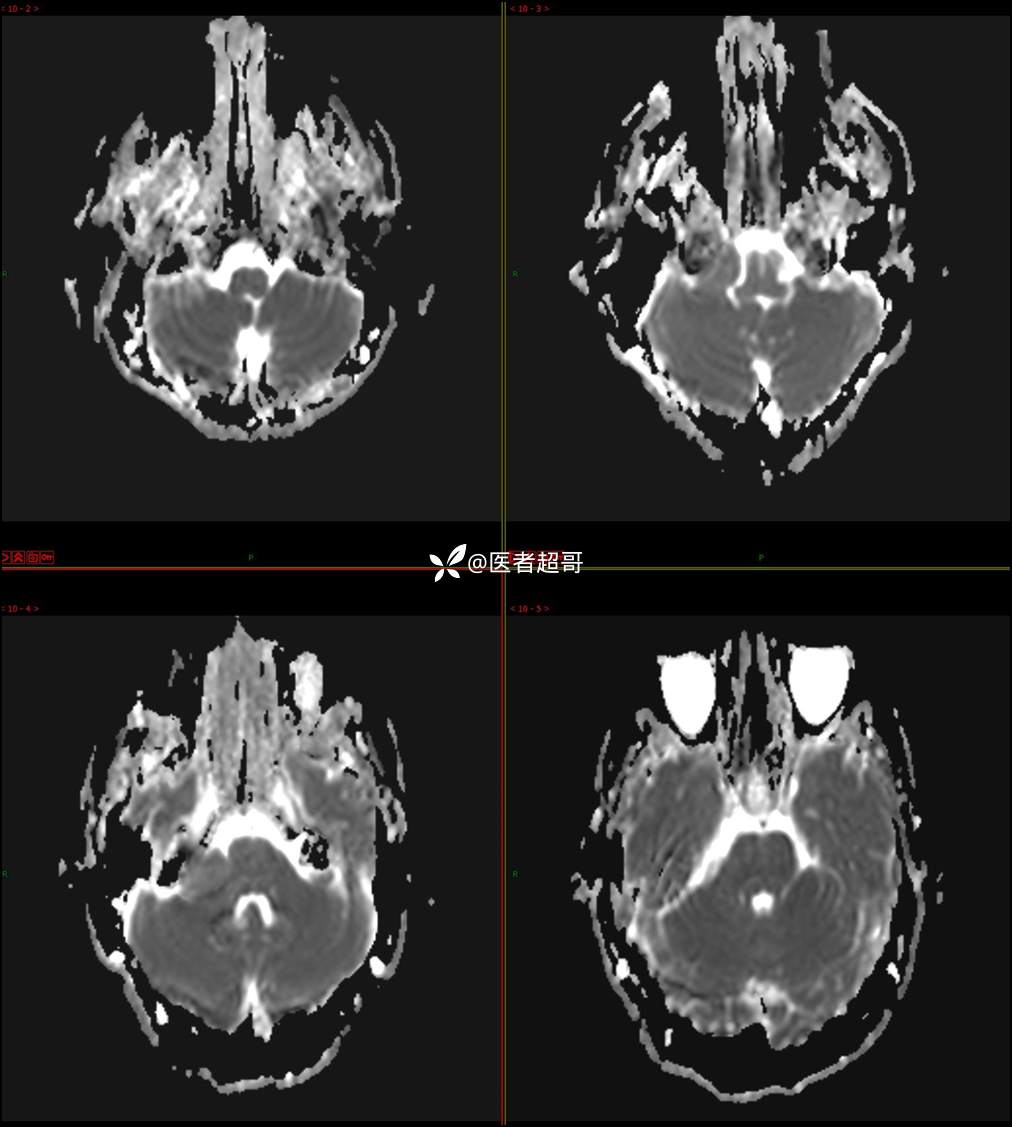

CPA区占位,是鞘瘤?脑膜瘤?请赏析!

现病史:患者3年前出现耳鸣,蝉鸣音,反复发作,夜间自觉明显,于2018年8月至我院耳鼻喉科就诊,行颅脑CT检查未发现明显异常改变,给予对症处理(具体不详);4天前突发头晕,伴明显恶心,至市人民医院就诊,行颅脑CT未见明显异常,颅脑MRI发现右侧桥脑小脑角区占位性病变。本次发病来无明显头痛,无肢体抽动,无大小便失禁。为求进一步诊治,遂来我院门诊,以“听神经良性肿瘤”收住入院。发病来,患者神志清,精神可,二便正常,饮食可,睡眠不佳,近期体重无明显变化,否认癫痫发作病史。